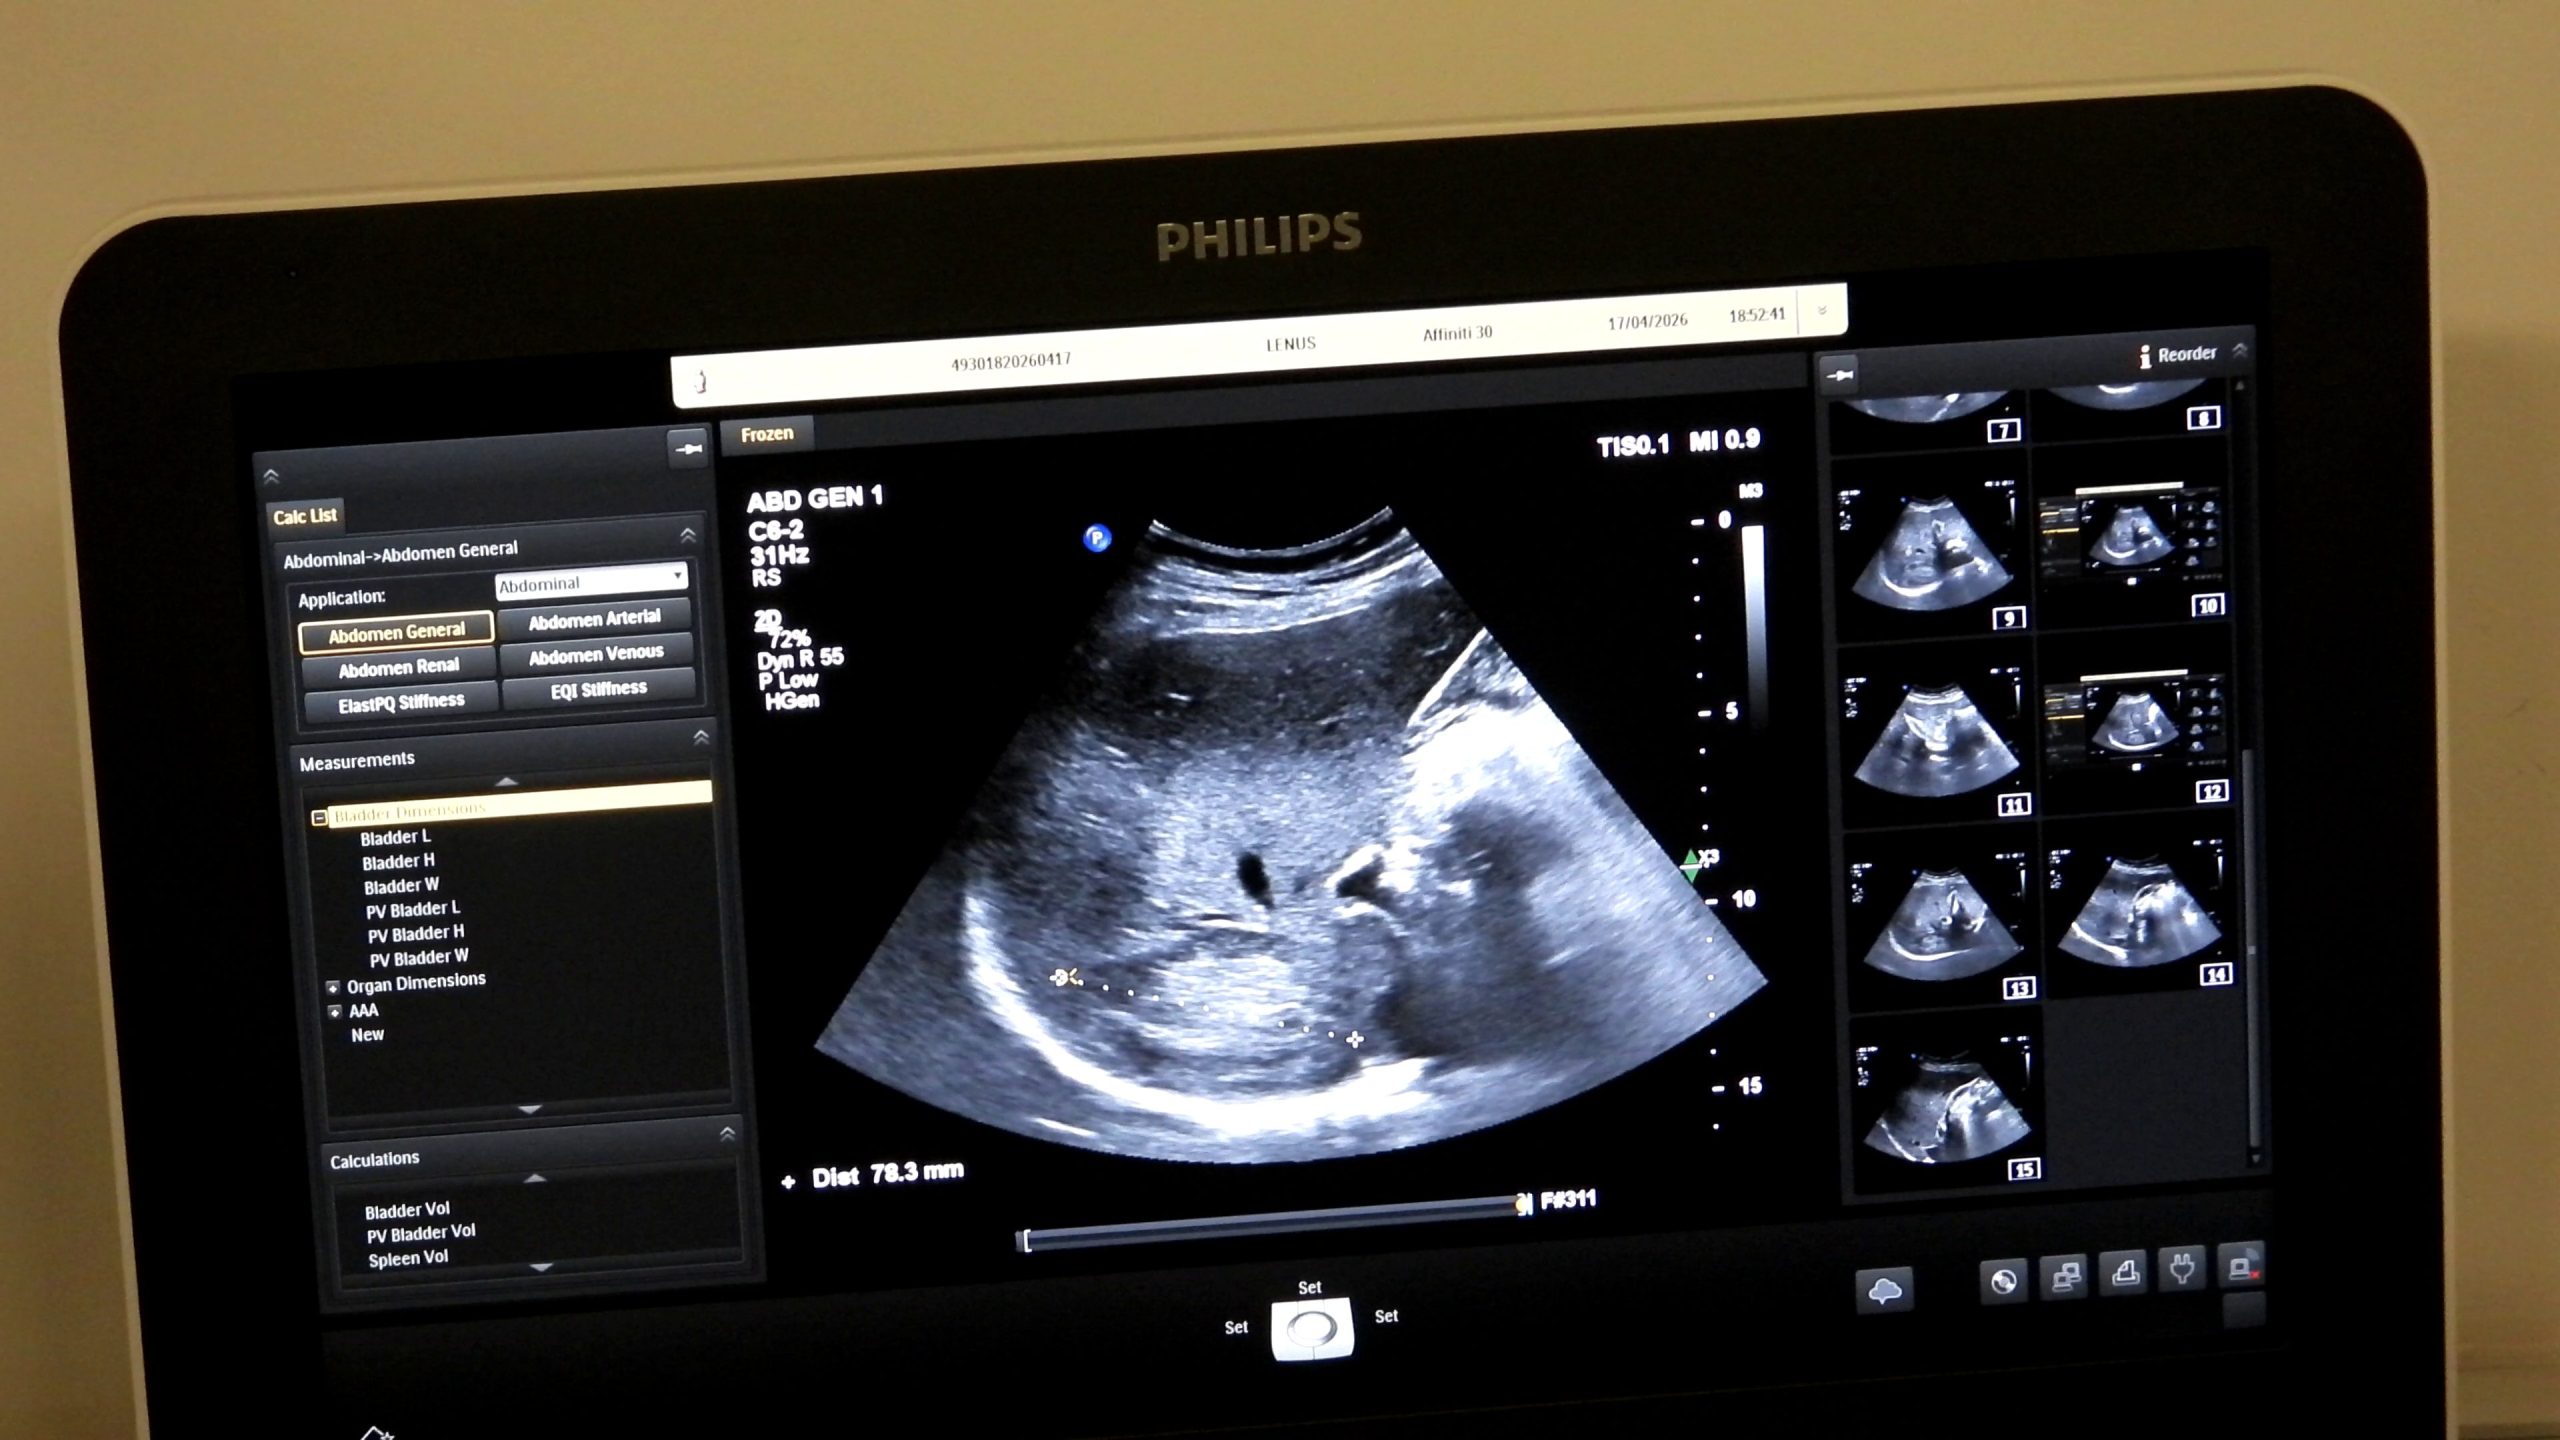

Novi obučeni ljekari skraćuju liste čekanja i jačaju preventivu – Završen drugi napredni kurs ultrazvuka abdomena u ZDK

U edukacionom centru Kantonalne bolnice Zenica uspješno je okončan drugi napredni kurs ultrazvuka abdomena u Zeničko-dobojskom kantonu (ZDK), čime je zaokružen ciklus kontinuirane edukacije ljekara započet prošle godine ranijim bazičnim kursevima i preventivnim aktivnostima. Završetkom ovog kursa još devet ljekara, odnosno ukupno 18 ljekara steklo je certifikate za samostalan rad u ultrazvučnoj dijagnostici abdomena, što predstavlja značajan iskorak u povećanju dostupnosti dijagnostičkih pregleda i jačanju preventivne zdravstvene zaštite u lokalnim zajednicama.

Edukacijom se stvara veći broj educiranih doktora koji mogu samostalno i sigurno raditi ultrazvučne preglede, što direktno povećava dostupnost dijagnostičkih pretraga pacijentima. Što više obučenih ljekara imamo, to su liste čekanja kraće, a građani brže dolaze do pregleda, posebno kada je riječ o preventivnim kontrolama. Organizatori su zahvalili kompaniji Farmavita na podršci realizaciji edukacije, kao i Philipsu, koji je ustupio dodatne uređaje za edukaciju.

Uz Kantonalnu bolnicu Zenica u projektu su učestvovali Ministarstvo zdravstva i Ljekarska komora ZDK, kompanije Farmavita i Philips, te Institut za zdravlje i sigurnost hrane Zenica. Dio vizije kontinuirane edukacije jeste jačanje zdravstvenog sistema u smislu dostupnosti ove dijagnostičke metode pacijentima u njihovim lokalnim zdravstvenim ustanovama. Prema podacima organizatora, certifikate su dobili doktori Alen Mahić, Sabina Bašić, Hana Torlak, Farisa Babić Šabanović, Mirel Čizmić, Dževad Velagić, Dragan Radoš, Selmir Osmanbegović i Belmin Prasko.